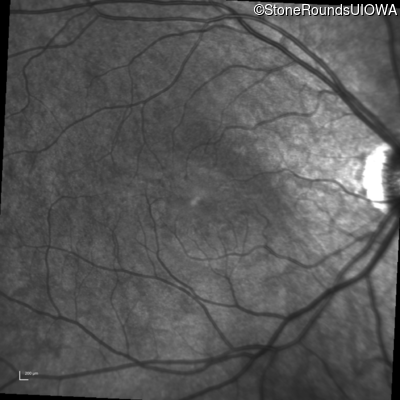

Infrared Fundus Photograph - Right - 20/40 +1

Exemplar